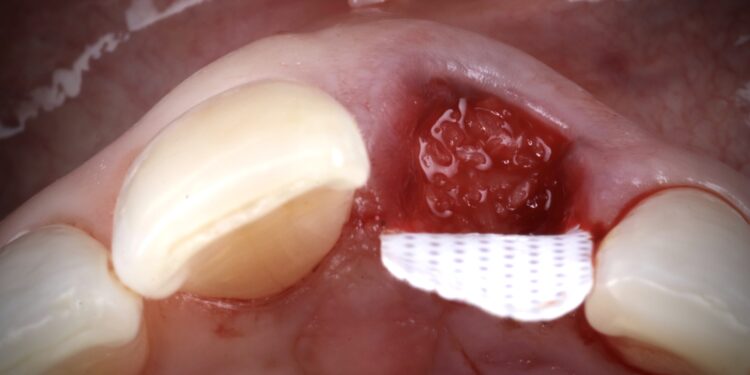

It was thus decided to carry out a ridge preservation graft to retain the existing alveolar ridge width and to use an open healing concept to encourage new soft tissue growth, increase keratinised tissue and avoid distortion of the mucogingival junction. This was carried out using the combination of MinerOss® Blend Allograft and a dense PTFE membrane.